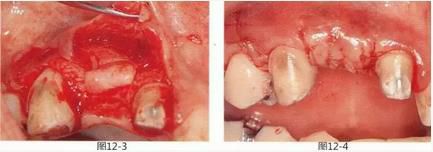

圖12-3   從右側腭部采集結締組織瓣,使用吸收性縫合線在通過骨膜縫合固定在牙槽骨缺失部。

圖12-4  縫合后變回齦瓣的狀態(tài)。